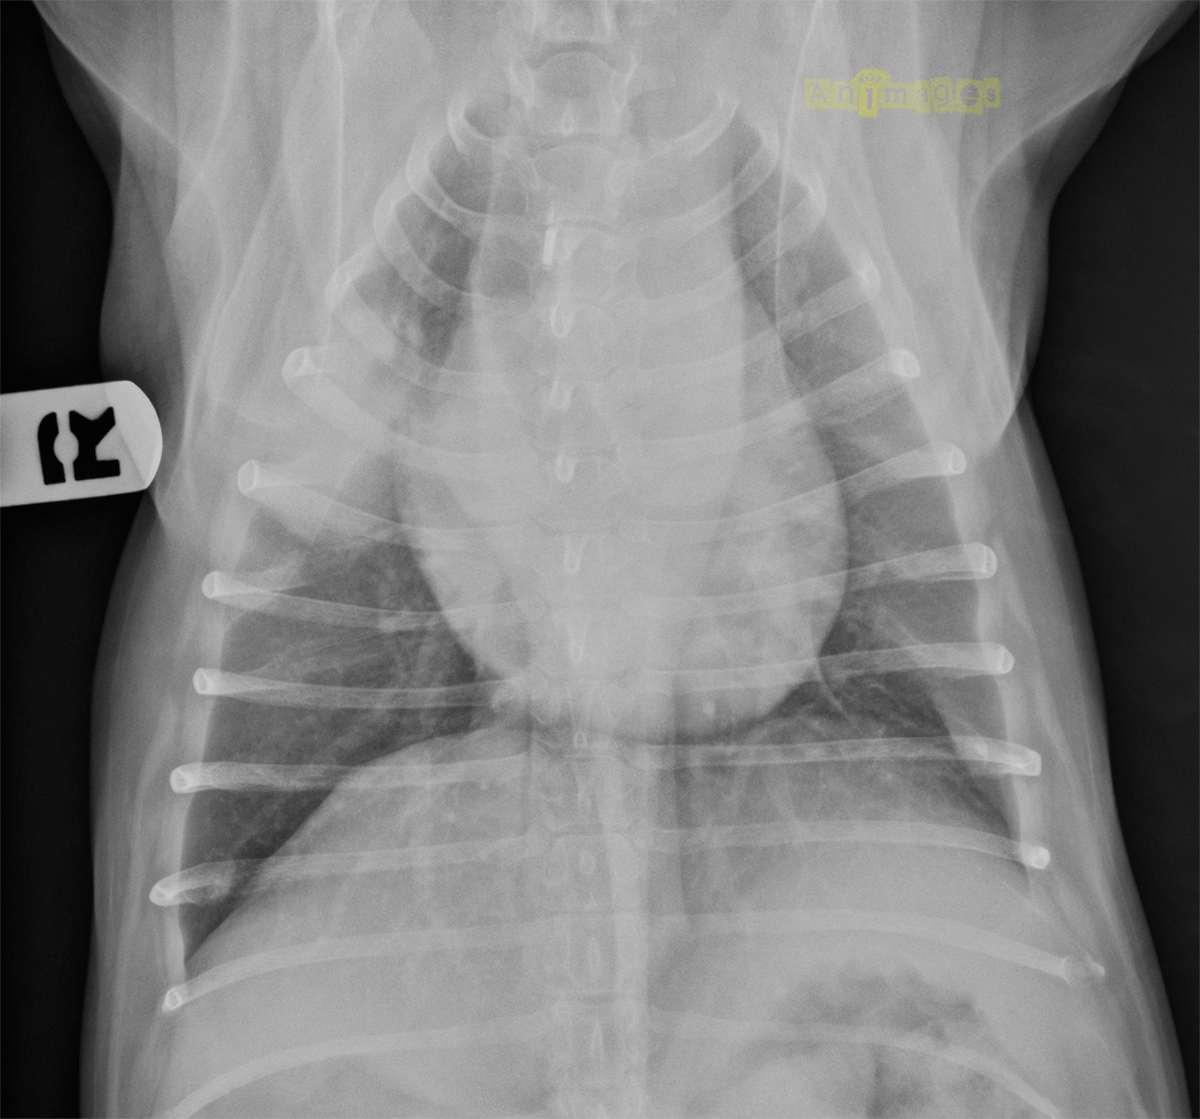

Dorsoventrale